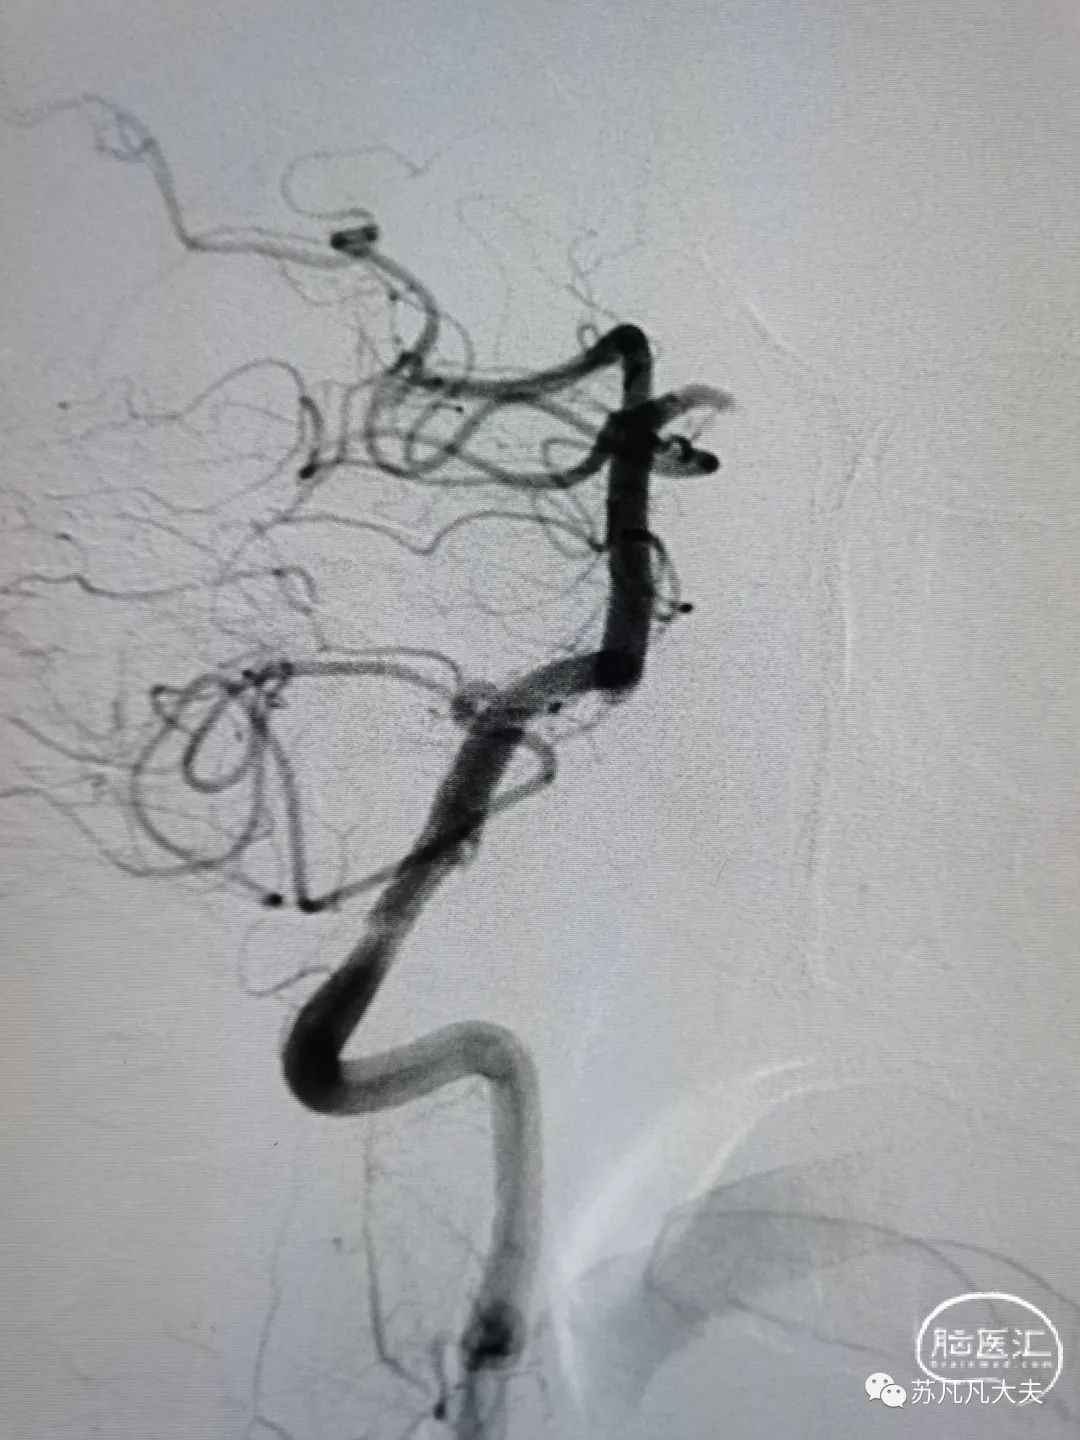

DSA示右椎发育不良,颅内段闭塞

DSA示左椎优势,V4段极重度狭窄,左侧大脑后动脉未显影

脑血管造影提示

患者右椎发育不良,左椎优势,颅内段极重度狭窄,狭窄远端存在双侧小脑后下动脉,导致低灌注,同时左侧大脑后动脉未显影,考虑系狭窄基础上血栓形成后脱落致大脑后动脉栓塞。

术后造影狭窄解除,颅内血供改善